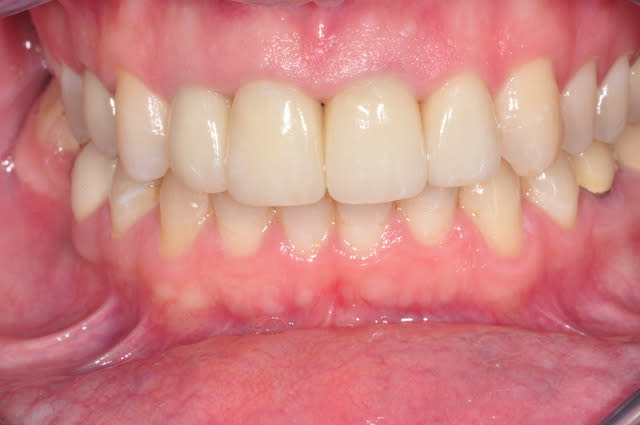

Bonjour,

savez-vous quelle est la raison de cette porosité de surface ?

il s'agit d'emax sur 11 21 22.

non en fait ma question porte sur l'état de surface de mes emax,

la coloration est présente depuis un bon moment et je n'en connais pas l'origine